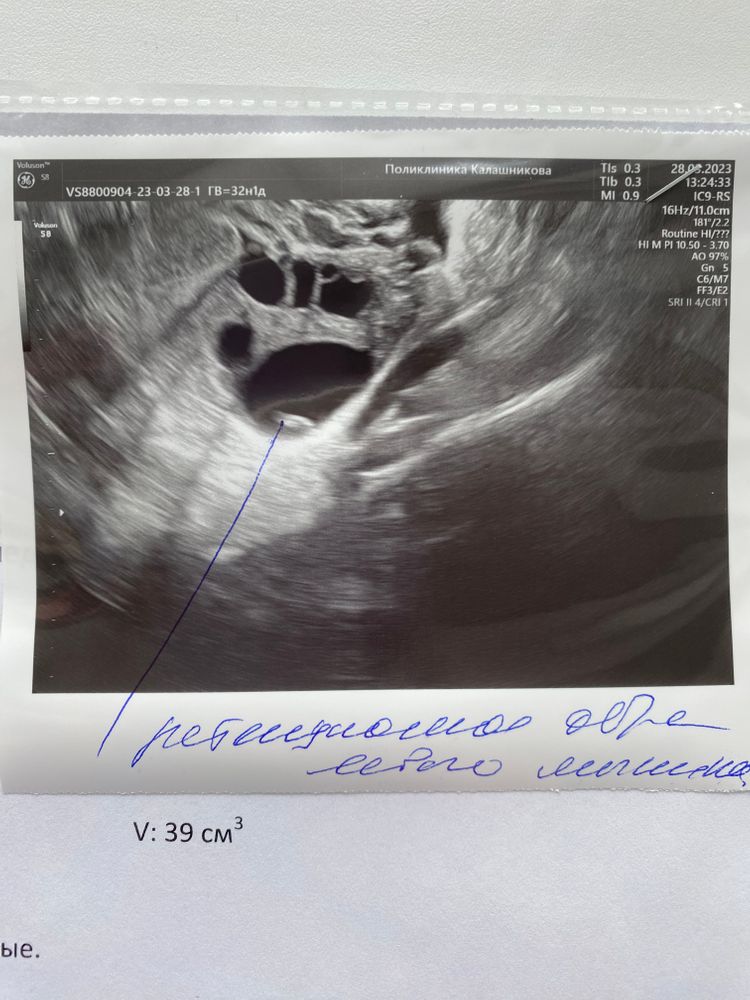

Emili в Хочу малыша 3 года Домашние животные: влияние на здоровье и благополучие Посмотрите еще 20 записей на эту тему Лучший ответ Екатерина У меня было 30мм, и уже лопнул в конце цикла а на узи увидели желтое тело. Так что все бывает. Только очень больная О была, из-за размеров... 28.03.2023 Ответить Отменить Ответить Лиса Обычно после 24мм считают фолликулярной кистой. т.е. у вас сутки ещё на овуляцию 28.03.2023 Ответить Emili Лиса, от 30 киста 24*15 в диаметре 19,5 28.03.2023 Ответить Овариум-Композитум, и через месяц стимуляция Клостом🙏❤️ ХГЧ, 13дпп Чаты Беременных Выберите чат: Январята-2026 Февралята-2026 Мартята-2026 Апрелята-2026 Майчата-2026 Июнята-2026 Июлята-2026 Августята-2026